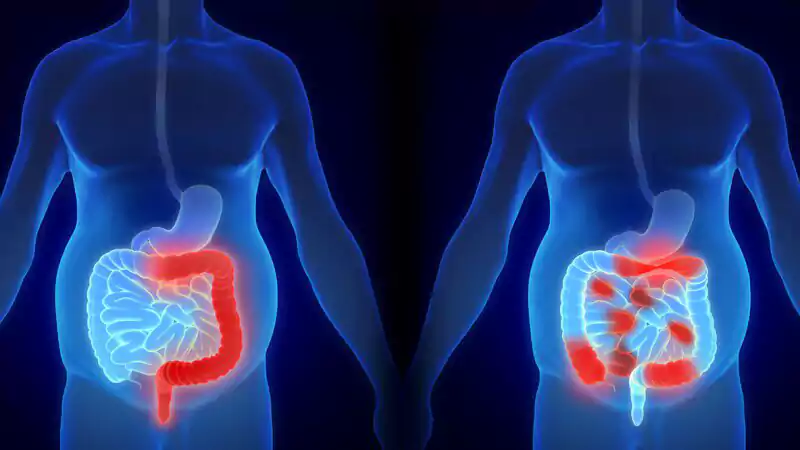

اما نکته نگرانکننده اینجاست: موارد ابتلا به سرطان روده بزرگ و راستروده در بزرگسالان زیر ۵۰ سال با سرعتی هشداردهنده در حال افزایش است.

این بیماری اکنون علت اصلی مرگومیر ناشی از سرطان در مردان ۲۰ تا ۴۹ ساله در ایالات متحده و دومین علت مرگ در زنان همین گروه سنی است. اگرچه غربالگری و روشهای تشخیص سرطان پیشرفت چشمگیری داشته، اما متخصصان میگویند افزایش موارد ابتلا تنها با بهبود روشهای تشخیص قابل توضیح نیست.

سرطان یک بیماری پیچیده است و افزایش موارد سرطان روده بزرگ و راستروده در افراد زیر ۵۰ سال احتمالاً ناشی از چندین عامل مختلف است. اگرچه ژنتیک در بخشی از موارد نقش دارد، اما متخصصان معتقدند که بیشتر ابتلاها در این گروه سنی به محیط و سبک زندگی مرتبط است.